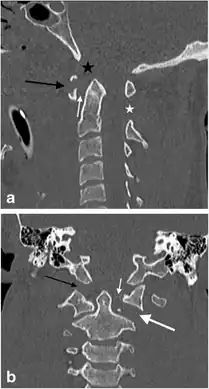

A Jefferson fracture is a bone fracture of the anterior and posterior arches of the C1 vertebra,[1] though it may also appear as a three- or two-part fracture. The fracture may result from an axial load on the back of the head or hyperextension of the neck (e.g. caused by diving), causing a posterior break, and may be accompanied by a break in other parts of the cervical spine.[1]

The diagnosis of a Jefferson fracture is done via radiographs of cervical spine (anteroposterior , lateral, oblique, and odontoid views)[7]